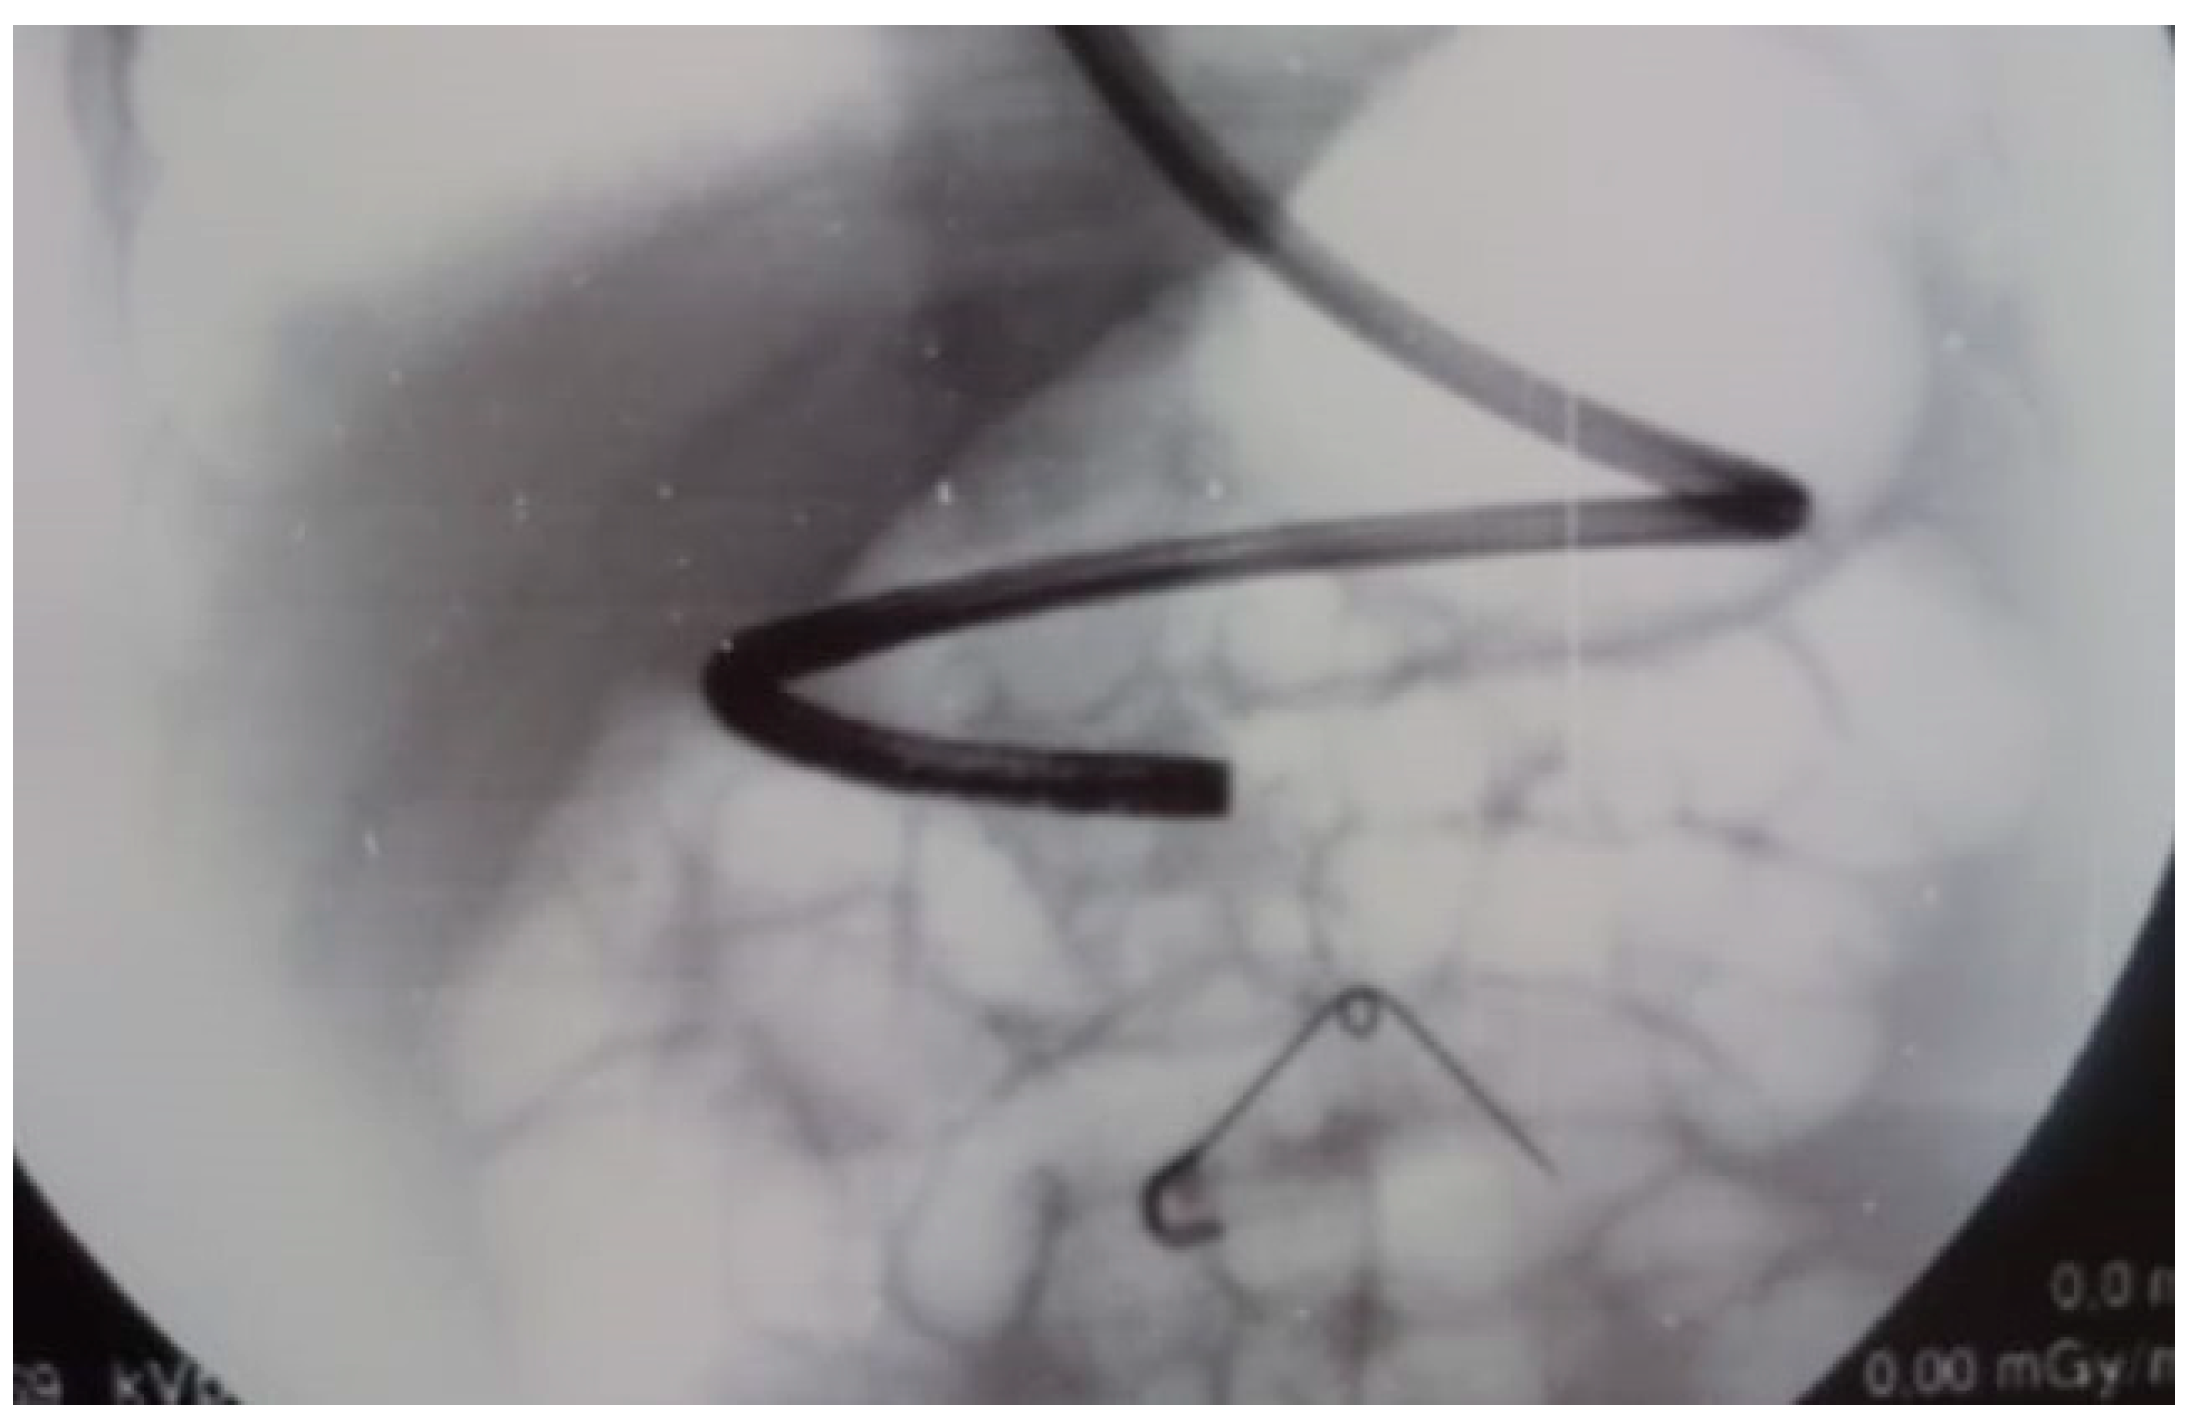

4. Endoscopic Retrograde Cholangiopancreatography (ERCP) and Laparoscopic Abdominal Surgery

- Turcu, F. The laparoscopic approach to cholecysto-choledocholithiasis.The “rendez-vous” technique. Chirurgia 2000, 95, 463–467. [Google Scholar]

- Rancan, A.; Andreetta, M.; Gaio, P.; Cananzi, M.; Rossoni, R.; La Pergola, E.; Fascetti Leon, F.; Gamba, P. “Rendezvous” Procedure in Children with Cholecysto-Choledocholithiasis. J. Laparoendosc. Adv. Surg. Tech. A 2019, 29, 1081–1084. [Google Scholar] [CrossRef]

- Cianci, P.; Restini, E. Management of cholelithiasis with choledocholithiasis: Endoscopic and surgical approaches. World J. Gastroenterol. 2021, 27, 4536–4554. [Google Scholar] [CrossRef] [PubMed]

- La Greca, G.; Barbagallo, F.; Di Blasi, M.; Di Stefano, M.; Castello, G.; Gagliardo, S.; Latteri, S.; Russello, D. Rendezvous technique versus endoscopic retrograde cholangiopancreatography to treat bile duct stones reduces endoscopic time and pancreatic damage. J. Laparoendosc. Adv. Surg. Tech. A 2007, 17, 167–171. [Google Scholar] [CrossRef] [PubMed]

- Arezzo, A.; Vettoretto, N.; Famiglietti, F.; Moja, L.; Morino, M. Laparoendoscopic rendezvous reduces perioperative morbidity and risk of pancreatitis. Surg. Endosc. 2013, 27, 1055–1060. [Google Scholar] [CrossRef]

- Iodice, G.; Giardiello, C.; Francica, G.; Sarrantonio, G.; Angelone, G.; Cristiano, S.; Finelli, R.; Tramontano, G. Single-step treatment of gallbladder and bile duct stones: A combined endoscopic-laparoscopic technique. Gastrointest. Endosc. 2001, 53, 336–338. [Google Scholar] [CrossRef]

- La Barba, G.; Gardini, A.; Cavargini, E.; Casadei, A.; Morgagni, P.; Bazzocchi, F.; D’Acapito, F.; Cavaliere, D.; Curti, R.; Tringali, D.; et al. Laparoendoscopic rendezvous in the treatment of cholecysto-choledocholitiasis: A single series of 200 patients. Surg. Endosc. 2018, 32, 3868–3873. [Google Scholar] [CrossRef] [PubMed]